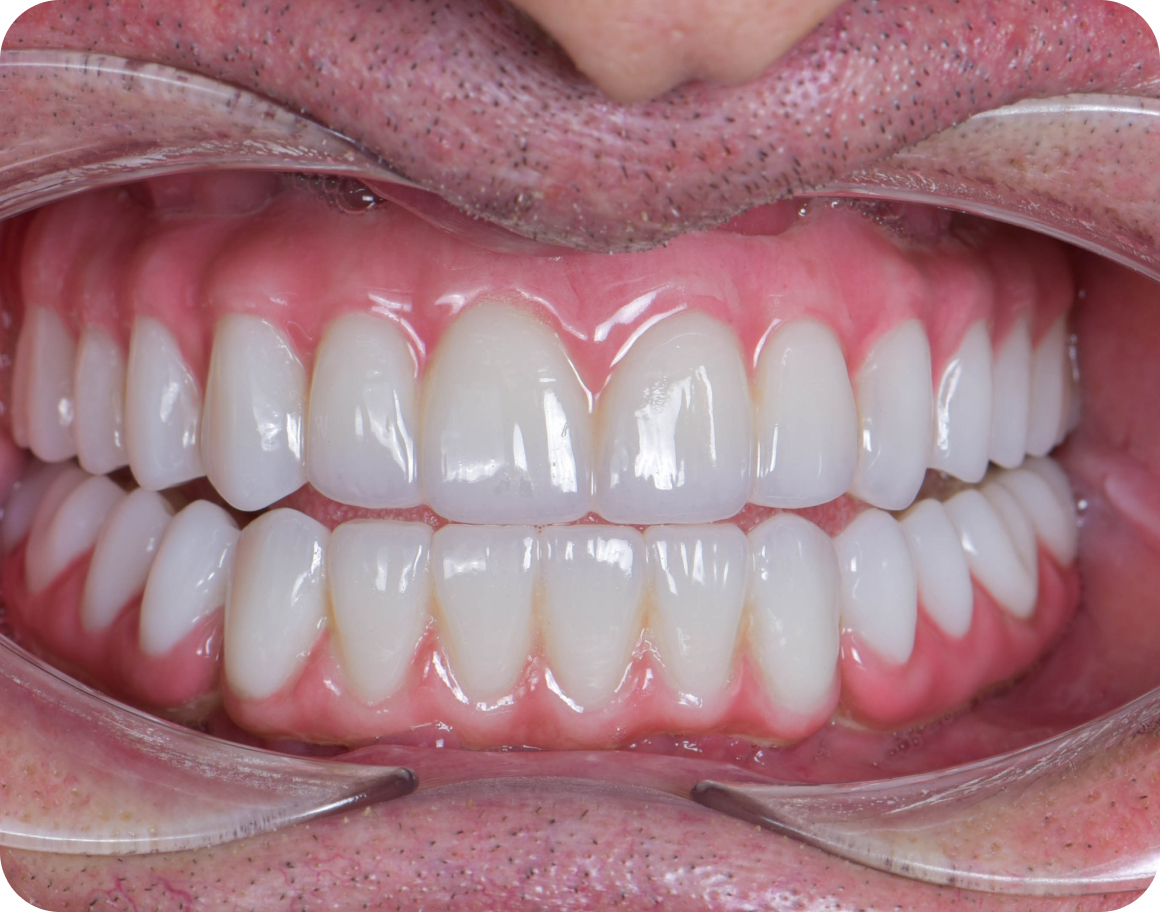

Улыбка до/после

Несъемные протезы

Циркониевый протез

• Высокая эстетика

• Срок службы 10-15 лет

• Хорошая прочность

Стоимость 400 000 ₽